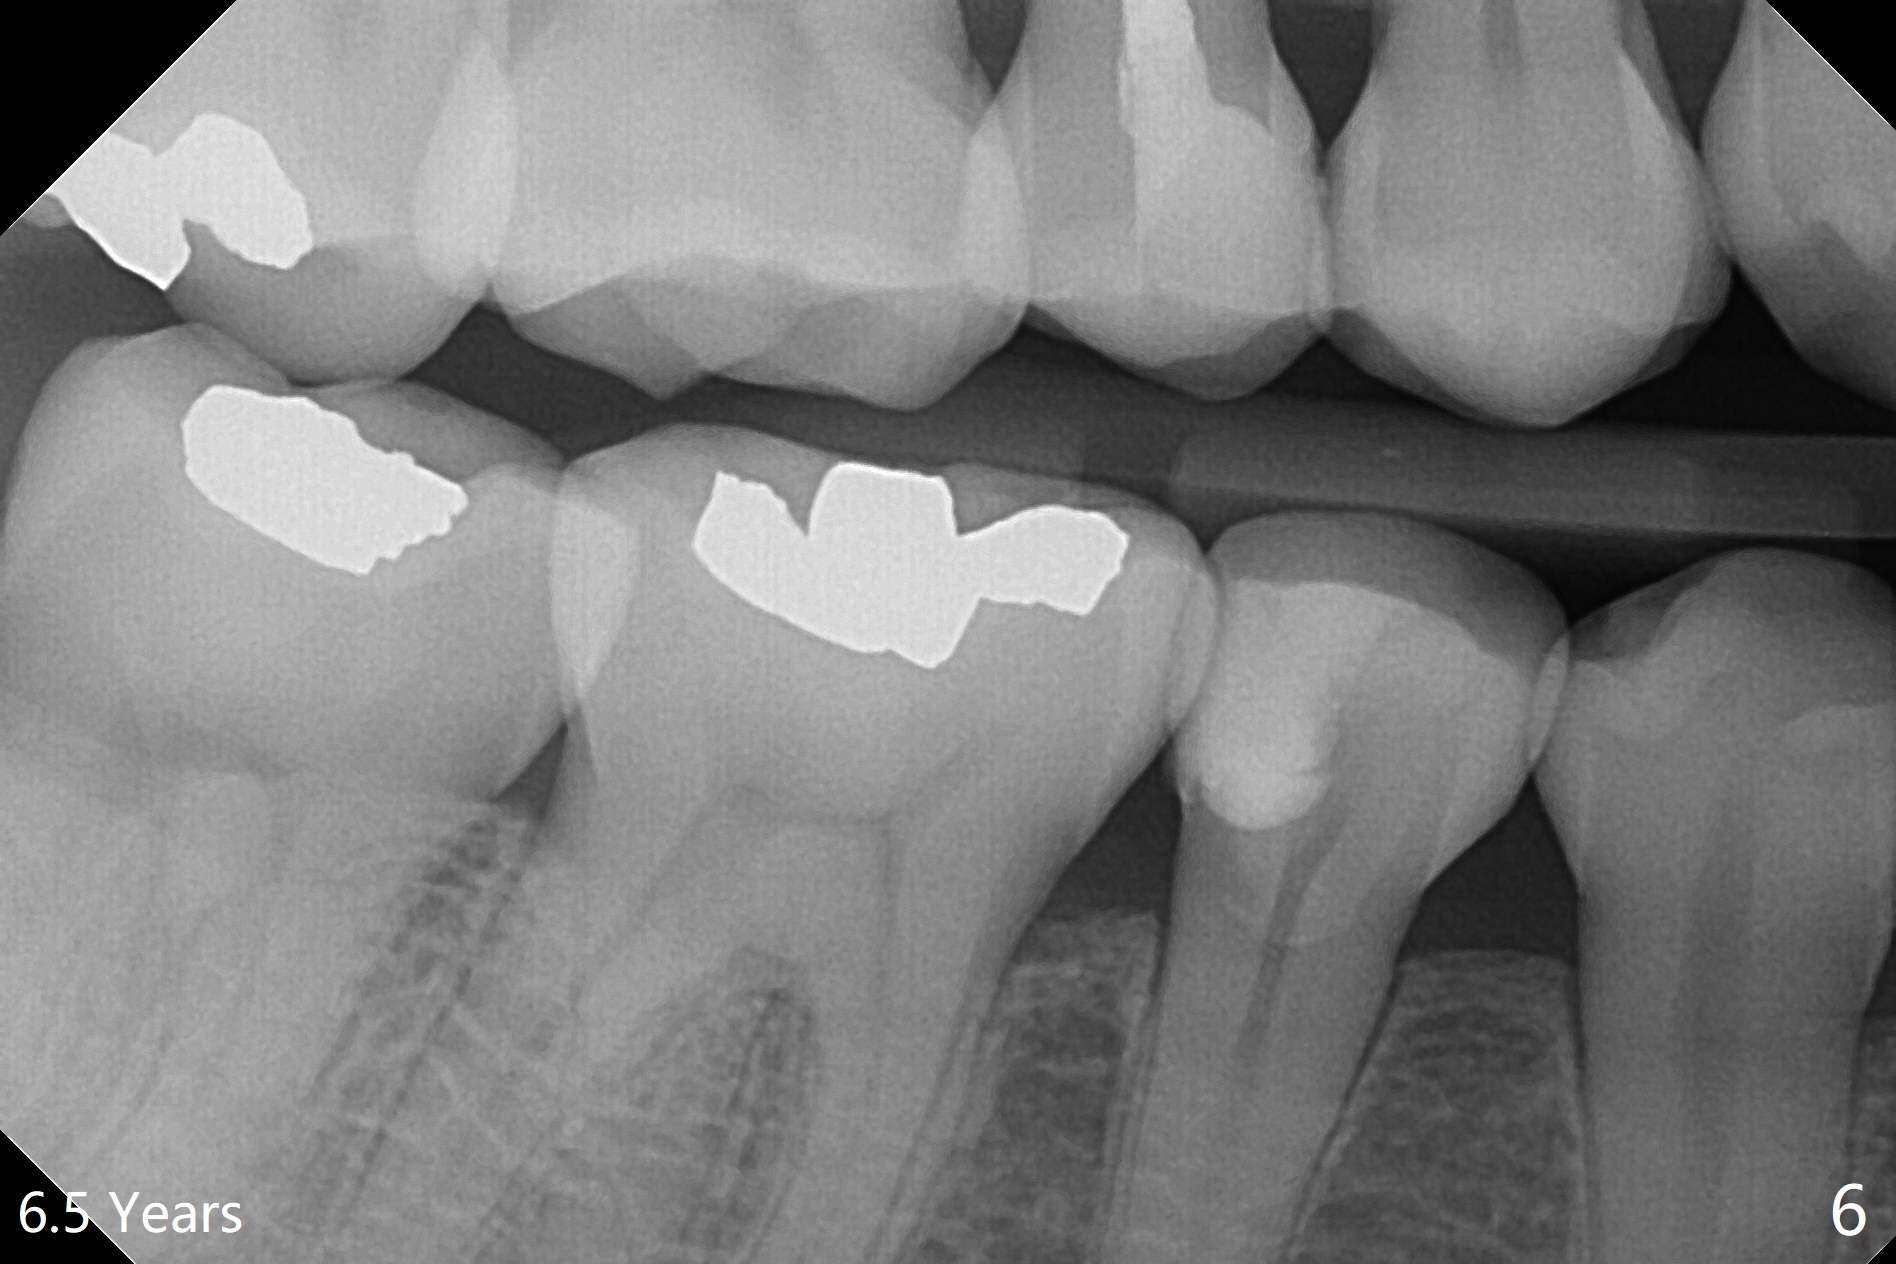

A 29-year-old woman presented to office with multiple amalgam restoration 7 years ago. The tooth #4 developed acute pulpitis 7 months later (Fig.2). The tooth has 2 fused canals; after RCT, composite was placed; after discussion, the patient chose no crown (Fig.3). There is no recurrent periapical radiolucency or tooth fracture 2.5 (Fig.4) or 6.5 (Fig.5,6) years postop.